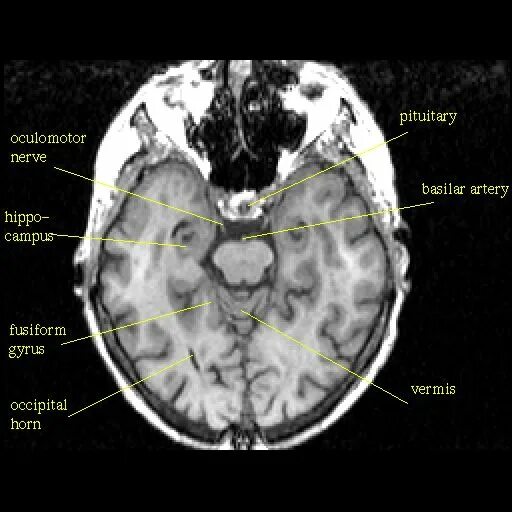

Цистерны на кт